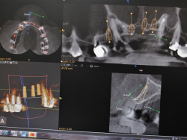

Cet examen reconstitue  en trois dimensions les  maxillaires supérieus et inférieurs , assure  un diagnostic plus fiable, et une meilleure qualité de traitement, notamment pour la chirurgie des implants.

A partir de cet examen, grâce à son logiciel intégré, nous réalisons une planification implantaire assistée par ordinateur (P.I.A.O), nous permettant de rendre prévisble le résultat final.